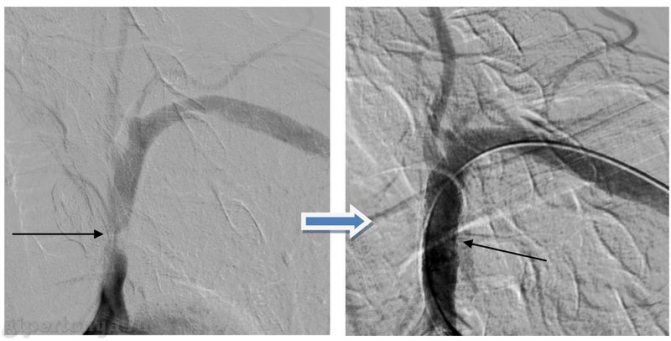

- Когда уровень кровяного давления на руке значительно меньше, чем на нижней конечности, то это может свидетельствовать о проблемном кровоснабжении верхней конечности. Такая аномалия может быть вызвана, например синдромом подключичного обкрадывания, который возникает в результате образования атеросклеротической бляшки.

Это зависит от размера используемой манжеты, а также от того, измерялось ли давление прямым (с использованием внутриартериального катетера) или непрямым (основанном на выслушивании тонов Короткова) методом. Если используется бедренная манжета нужного размера, то измеренное в подколенной ямке систолическое давление может или равняться зарегистрированному на руке, или быть выше его.

В последнем случае разница между величинами давления может достигать 20 мм рт. ст. Если систолическое давление на ногах ниже, чем на руках, то следует заподозрить обструктивное поражение аорты ниже места отхождения подключичных артерий или же стенозирование магистральных артерий нижних конечностей [76J.

б. Возникающие при компрессии бедра манжетой дискомфортные ощущения могут быть достаточно интенсивными и вызвать транзиторное повышение кровяного давления. В тех случаях, когда необходимо тщательное сравнение артериального давления на руках и ногах (например, у больных с подозрением на коарктацию аорты или аортальную регургитацию), соответствующие измерения должны осуществляться двумя наблюдателями одновременно.